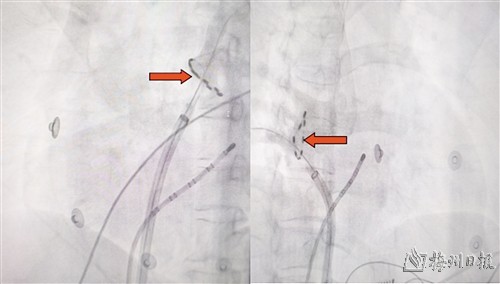

实施圣达济脉冲电场消融,箭头所指为脉冲电场消融导管。

脉冲消融术前术后肺静脉隔离效果对比图。(医院提供)

在钟志雄教授指导下,经过充分的术前准备,张奇峰主任医师团队如期为张姨开展脉冲电场消融手术。手术团队将消融导管送入指定位置进行消融治疗,一次消融时间仅2秒钟,经过多部位的消融,房颤电位消失,心脏恢复正常规律跳动。整个消融过程用时仅半个多小时,术后患者恢复顺利,房颤未再发作。